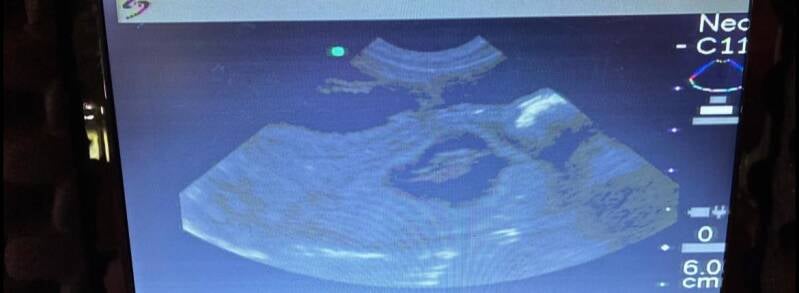

We zijn ontzettend blij om te delen dat Maya in verwachting is! πŸ’•

Als alles goed gaat, verwachten we eind juni prachtige kleine wondertjes.